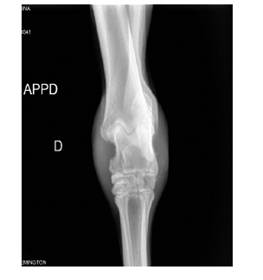

En el abordaje anteroposterior se encuentra proliferación ósea y reacción perióstica del maléolo medial de la tibia, con Figura 3. Radiografía anteroposterior de tar-superficie irregular y disminución de la denso de equino hembra de 4 años con historial sidad, así como para el aspecto medial y late-de trauma en la región del tarso del miembro ral del astrágalo. Se observa disminución del posterior derecho. Se observa reacción espacio articular entre las articulaciones proliferativa en la región distal de la tibia y intertarsianas proximales e intertarsianas generalizada en el astrágalo, con pérdida de distales, lisis óseas en el cuarto hueso tarsiano, los espacios articulares y zonas de lisis ósea y aumento de tamaño del tejido blando en los aspectos mediales y laterales de la articulación tarsiana (Figura 3). En la radiografía lateral del menudillo se encuentra luxación de la articulación interfalángica proximal, mientras que los sesamoideos proximales presentan un patrón apolillado con múltiples zonas focales de lisis ósea y pérdida de densidad.

Figura 3 Radiografía anteroposterior de tarso de equino hembra de 4 años con historial de trauma en la región del tarso del miembro posterior derecho. Se observa reacción proliferativa en la región distal de la tibia y generalizada en el astrágalo, con pérdida de los espacios articulares y zonas de lisis ósea